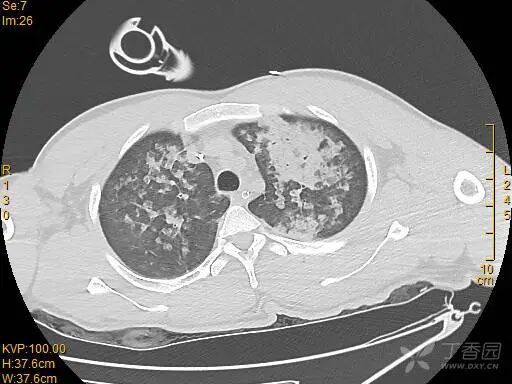

胸部 CT 如下:

图片